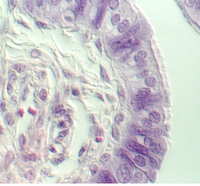

The cervix continues and joins with the vagina. The cervix is lined by simple high columnar epithelium which consists of mucous cells. These are shown in the following views. In the lowest magnification, one can see bundles of smooth muscle in the wall (see below)